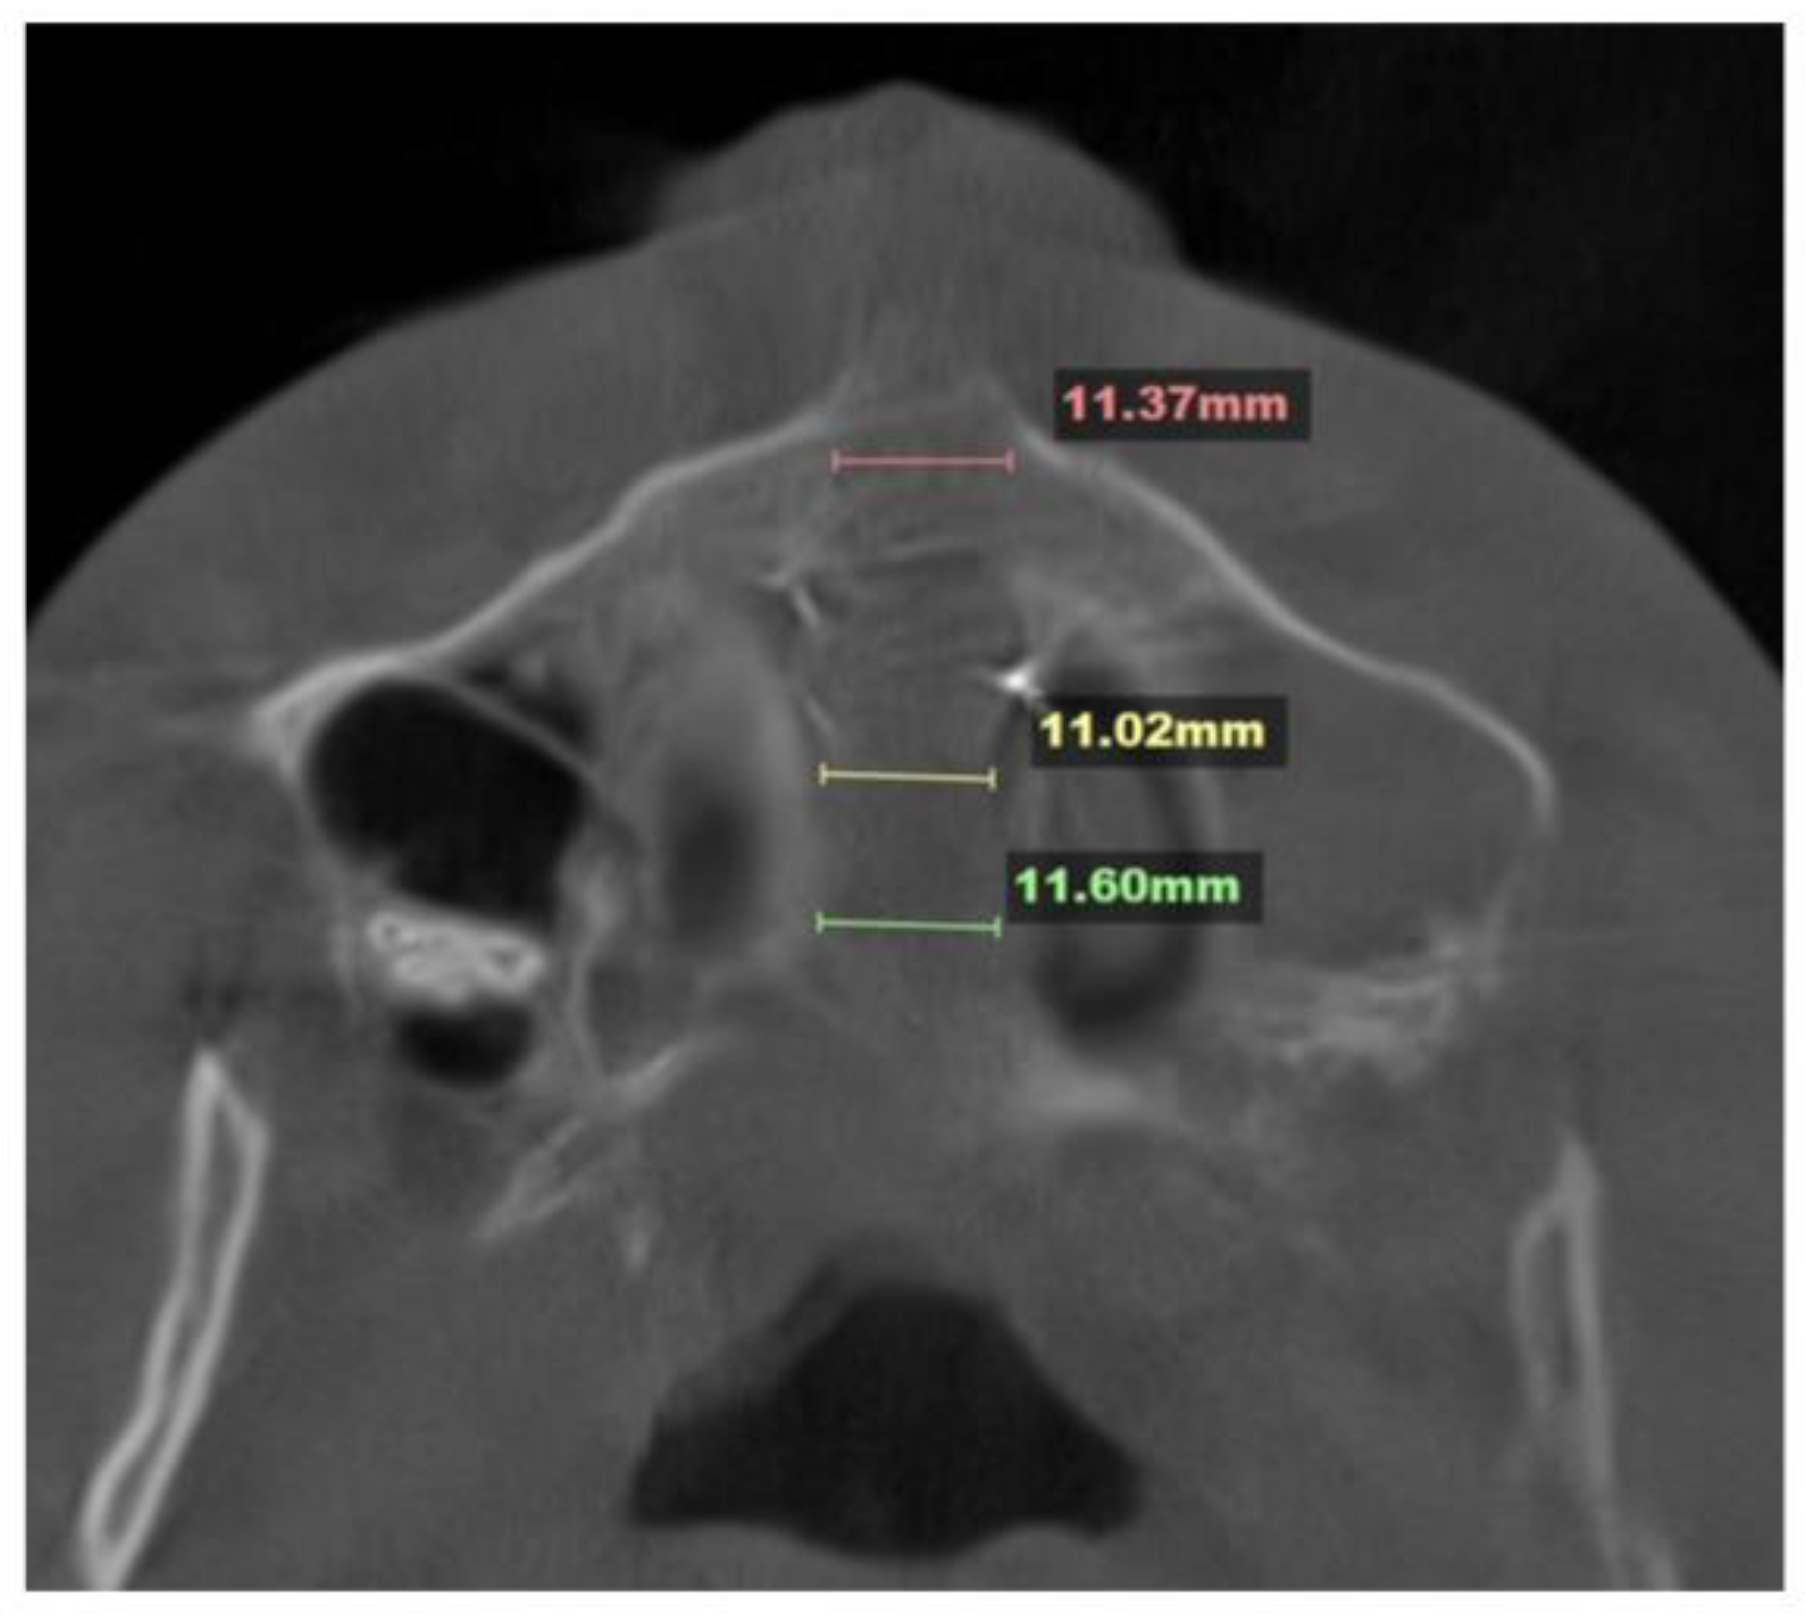

The midpalatal suture disarticulation was measured at three points: the ANS, the middle third of the suture, and the PNA. The mean disarticulation was 11.33 mm (Fig. 4).

The midpalatal disarticulation resulted in parallel separation of the midpalatal suture at all points, including the ANS and PNS (Fig. 4).

Figure 4. Disarticulation of the midpalatal suture with parallel separation at the level of the ANS and PNS.